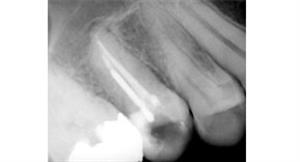

Root Canal Treatment

Before

After

A root canal procedure (endodontic treatment) is often required to save an infected tooth. Bacteria can enter a tooth through a cavity or a damaged filling. When this happens, the tooth can become abscessed, meaning the pulp inside the tooth becomes infected. An abscessed tooth can be quite painful and cause swelling in the surrounding gum tissues. If left untreated, it can cause several oral health problems. A root canal procedure removes the infected pulp and any other infected tissues within the tooth.